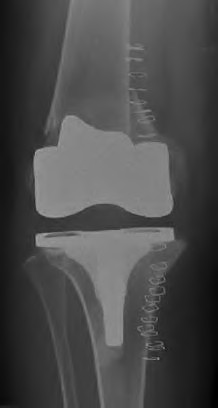

A 64-year-old woman with osteoarthritis underwent bilateral total knee replacement 3 years ago. Current radiographs are shown in Figure A. She reports a 3-month history of bilateral knee pain while at rest and increasing swelling in the knees. Her ESR and CRP are elevated and bilateral knee aspiration cultures reveal Staphylococcus aureus. What is the most likely outcome if the patient undergoes simultaneous, bilateral knee resection arthroplasty with cement spacer and a course of intravenous antibiotics?

This patient presents with bilateral total knee arthroplasty infection.

Wolff et al report Level 4 evidence of 18 patients followed an average of 5 years after bilateral TKA infection. Eleven patients were initially treated with attempts to salvage the original prosthesis (polyethylene l liner exchange, I&D, IV antibiotics and chronic oral suppressive antibiotics. With prosthesis retention, 9/11 (81%) developed recurrent infection at a mean of 15 months. The other 10 patients initially underwent resection arthroplasty with cement spacer and a course of IV antibiotics. Seven of the 10 (70%) underwent reimplantation at a mean of 3 months (6 weeks to 5 months) and none of the patients required revision at mean of two years follow up. Satisfaction rates were significantly higher among this group of patients. The authors advocate the protocol of bilateral TKA resection arthroplasty with cement antibiotic spacer and course of IV antibiotics followed by prosthesis reimplantation.